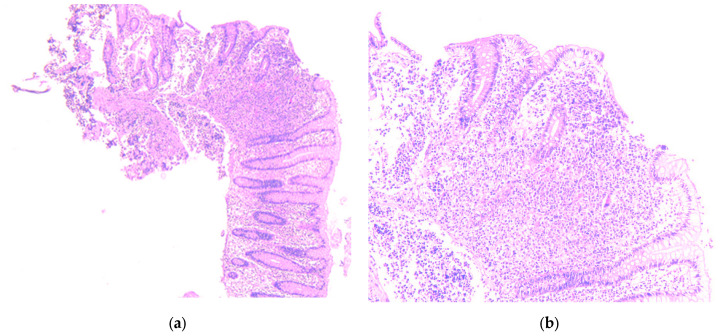

Background and Clinical Significance: Neuroendocrine neoplasms (NENs) are a group of malignancies that may remain clinically silent for many years. The presence of hepatic metastases can be the first clue leading to diagnosis. Case Presentation: We report the case of a 67-year-old man with intermittent tiredness and suspicious hepatic nodules detected on routine abdominal ultrasound. Contrast-enhanced ultrasonography showed arterial hyperenhancement with early washout, suggestive of metastases. Synchronous high-grade neuroendocrine carcinomas (NECs) of the lung and cecum were identified. Although the liver lesions were initially presumed to arise from the cecal tumor, liver biopsy immunohistochemistry was TTF-1 positive/CDX2 negative, whereas the cecal lesion was TTF-1 negative/CDX2 positive. This mutually exclusive immunophenotype confirmed two separate primary carcinomas. Given the high-grade histology, the patient received platinum-based chemotherapy and achieved a partial response. Conclusions: This case illustrates the diagnostic complexity of synchronous lesions and highlights the "mirage of the first lesion" phenomenon, in which the initially detected tumor may not represent the true primary site. A comprehensive, multidisciplinary strategy is crucial for establishing the correct diagnosis and guiding optimal management.